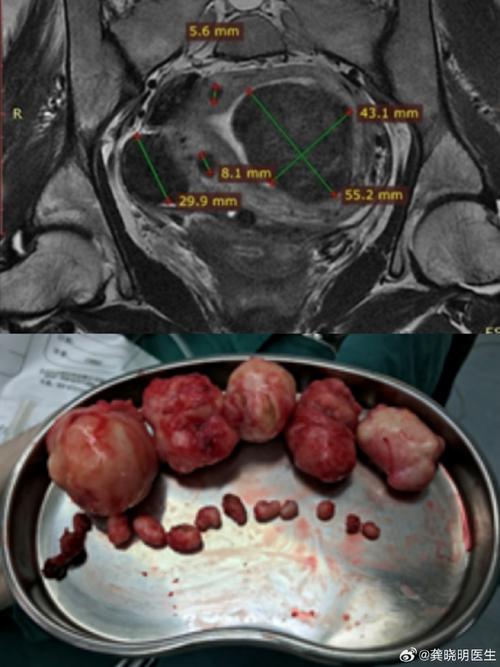

子宫肌瘤(又称子宫平滑肌瘤)是女性生殖器官中最常见的一种良性肿瘤,由平滑肌和结缔组织组成,它们的大小、数量和位置各不相同。

大多数患有子宫肌瘤的孕妇都能顺利度过孕期并生下健康的宝宝,但根据肌瘤的大小、数量、位置(尤其是是否在子宫腔内或宫颈口)以及生长速度,确实可能带来一些潜在的风险。

(图片来源网络,侵删)- 黏膜下肌瘤(向子宫腔内生长的肌瘤)对怀孕影响最大,可能会影响受精卵着床,导致早期流产或反复流产。

- 肌壁间肌瘤(位于子宫肌层内)如果较大或位置不佳,可能会影响子宫腔的形态和血供,增加流产和早产的风险。

大型肌瘤,特别是位于子宫下段的肌瘤,可能会占据胎儿的空间,限制胎儿的活动,导致胎位不正,如臀位、横位等。

- 如果肌瘤较大(如直径大于5厘米),或位于子宫下段、宫颈口等阻碍胎儿娩出的位置,医生通常会建议进行剖腹产,以确保母婴安全。